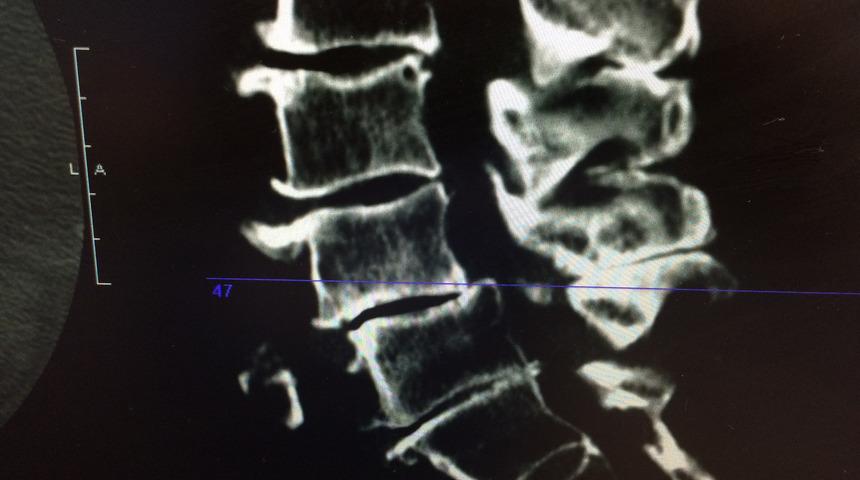

Omurga darlığı teşhis etmek için doktorunuz size işaretler ve semptomlar hakkında sorular sorar, tıbbi geçmişinizi araştırır ve fizik muayene yapar. Belirti ve semptomlarınızın nedenini belirlemenize yardımcı olmak için röntgen, MRI, BT gibi görüntüleme testi isteyebilir.

En sık bel ve boyunda görülen spinal darlık, bazı kişilerde semptom vermeyebiliyor. Görülen semptomlar ise; ağrı, karıncalanma, uyuşukluk ve kas zayıflığı. Belirtiler zamanla kötüleşebilir. Dar kanal, en sık omurga osteoartriti ile ilişkili aşınma ve yıpranma değişikliklerinden kaynaklanır. Şiddetli dar kanal vakalarında, doktorunuz omurilik veya sinirler için ek alan yaratmak için ameliyat önerebilir.